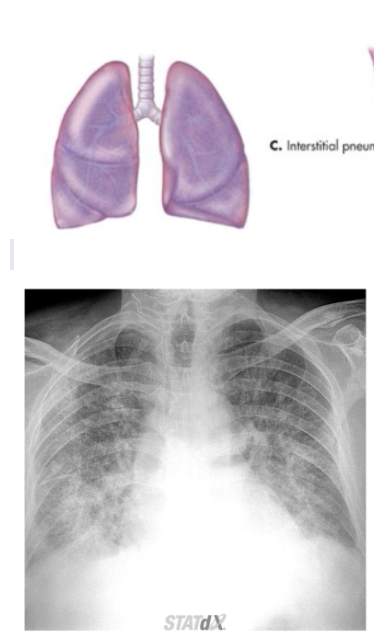

What CXR radiographic findings are typical for interstitial pneumonia

• Reticular interstitial disease, alveolar walls affected and usually diffuse throughout → Whole airspace consolidation